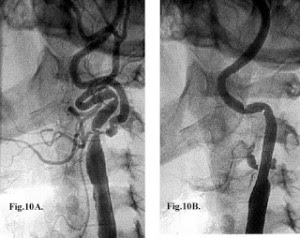

Если не верите - посмотрите.

На снимке извитые сосуды, заполненные контрастом.